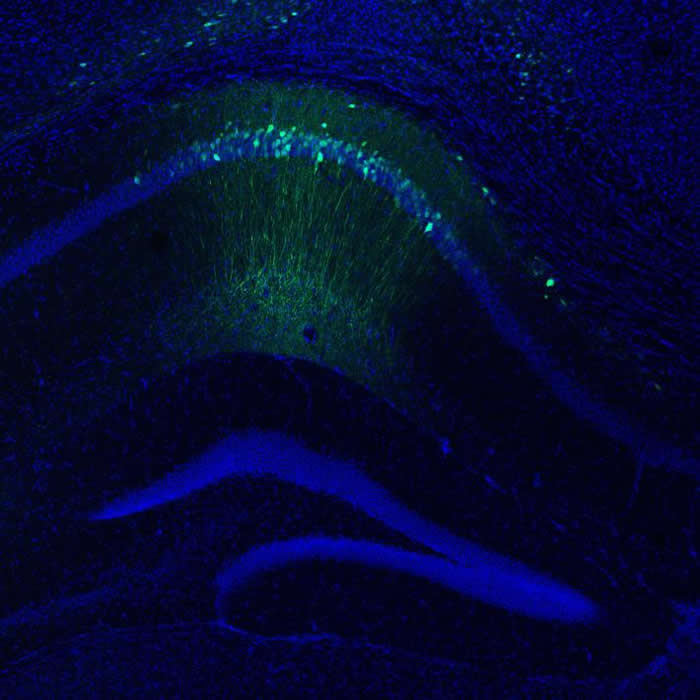

每张图中的绿色部分,都代表被萤光蛋白标示出「标记」记忆的地方。 PHOTOGRAPH BY STEPHANIE GRELLA

实验进行之前,会先在小鼠身上注射一种含有萤光蛋白的病毒,并在小鼠脑中放置光纤。 PHOTOGRAPH BY STEPHANIE GRELLA

当小鼠经历了正面、负面和中性的体验时,该蛋白就会绑定特定的记忆,让研究人员可以确定这段记忆储存在脑中哪个部位。 PHOTOGRAPH BY STEPHANIE GRELLA

为了替老鼠准备好进行实验,研究团队在小鼠脑部注射了含有萤光蛋白的病毒,并以手术植入光纤。之后小鼠会被给予可避免病毒发光的饮食,直到研究人员准备好标记一段正面或负面的经验。